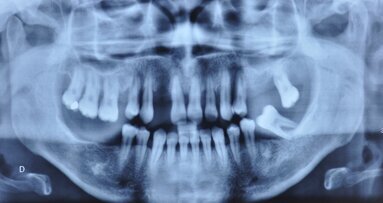

Il est également très important de joindre une radio panoramique. Nous agrafons sur la page 2 une lettre qui résume et liste les documents contenus dans ce dossier. Nous pouvons également encarter une carte de visite.

Lors du deuxième rendez-vous nous recevons notre patient et lui expliquons ce plan de traitement. Lorsqu’il est simple la secrétaire peut s’en charger. Par contre, pour les traitements complexes nous prenons le temps, environ 30 à 40 minutes pour expliquer le ou les plans de traitements que nous proposons. Nous le faisons alors devant une radiographie panoramique (écran ou négatoscope) et nous annotons sur la photocopie de la pano, remise au patient, les numéros des dents et schématisons éventuellement la position des implants. C’est important de le faire devant le patient, car de nouveau il prend conscience que vous traitez son dossier avec beaucoup de sérieux et d’attention. Vous pouvez penser que cela prend beaucoup de temps et que ce ne sont pas des minutes rémunératrices. C’est vrai si l’on raisonne à court terme. Par contre sur le long terme c’est « payant ». Le taux d’acceptation de nos plans de traitement est très élevé. Nous avons un taux de transformation de plus de 75 %. Il faut préciser à long terme, car certains accords peuvent être donnés plusieurs semaines à plusieurs mois après. Mais ceci s’explique par les sommes importantes que représentent les plans de traitement.